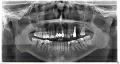

4 месяца поставили имплант, верх 7. Сейчас установили формирователь, но была болезненность. На следующий день врач снял формирователь, у меня воздух стал проходить из пазухи в рот, причем такое ощущение, что там большая дырка. Врач положил лекарство и сказал, что все должно затянуться, приходить через неделю ставить формирователь.

Бежать необходимо от таких горе-хирургов, срочно обратитесь к другому врачу. Перфорации пазухи на этапе формирователя быть не может. Там что-то не так.